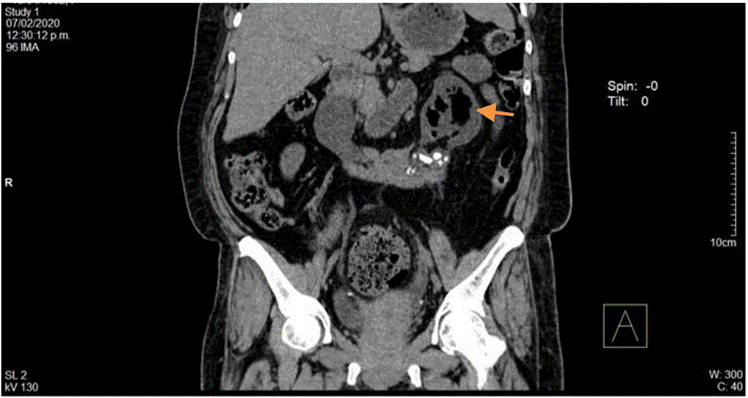

La ecografía abdominal total mostró hallazgos sugestivos de PNE izquierda (Figura 1), por lo que se solicitó valoración por urología; este servicio indicó continuar con la misma terapia antibiótica y realizar UROTAC que mostró microlitiasis renal bilateral, litiasis ureteral izquierda y proceso infeccioso inflamatorio con presencia de gas en el riñón izquierdo, lo que indicó diagnóstico de PNE izquierda tipo 2 (Figuras 2 y 3). Ante los hallazgos radiológicos y el reporte de urocultivo positivo para Escherichia coli multisensible, se decidió hacer rotación de cubrimiento antibiótico a carbapenémicos debido al alto riesgo de mortalidad.

Figura 2 UROTAC en el que se evidencia asimetría renal, riñón izquierdo aumentado con evidencia de múltiples zonas de acumulación de gas peri y pararrenal.

Figura 3 UROTAC en el que se evidencia riñón izquierdo de mayor tamaño con destrucción del parénquima y sustitución por material gaseoso.